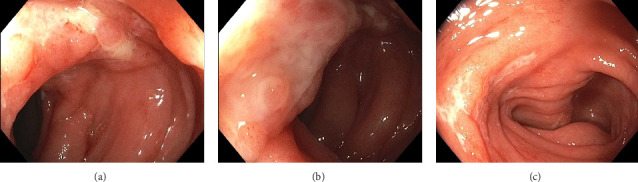

Diagnosing inflammatory bowel disease (IBD) can be challenging in the presence of mimicking conditions, such as infectious colitis. An accurate diagnosis is important to avoid unnecessary treatment. Nontyphoidal Salmonella species are an important cause of infectious colitis that at times can mimic IBD. Salmonella enterica serotype Saintpaul has caused numerous fatal foodborne gastroenteritis outbreaks worldwide. It has also been known to cause other infections, such as bacteremia, splenic abscesses, and meningitis, but has only rarely been known to cause colitis. Worryingly, antibiotic resistance rates of S. Saintpaul are rising. This case report presents a woman with S. Saintpaul colitis mimicking Crohn's disease. Despite an initial plan to start biologic therapy, long-term follow-up while off immunosuppressant therapy confirmed S. Saintpaul as the underlying cause of colitis, sparing our patient long-term immunosuppression. This case highlights the importance of ruling out infectious colitis before beginning long-term immunosuppressive therapy and the challenges of mimicking conditions as well as the novelty of the Saintpaul serotype causing colitis.

Abstract Image